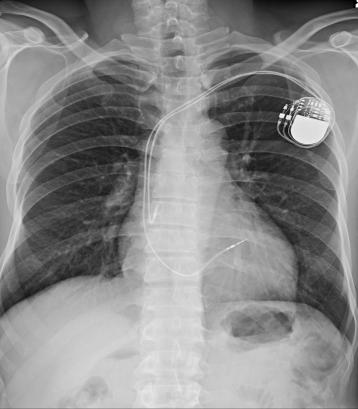

首先金属植入物产生影响(如心脏起搏器、金属支架等),可能会导致移位或发热,造成组织损伤或更严重的事故;MRI扫描中的射频能量可能会引起患者体内温度升高,这种温度变化可能带来风险,所以高热的人退热后进行检查;当需要做增强MRI检查,某些人可能有对比剂过敏风险;磁场非兼容性急救、医疗、维修、消防、清洁等工具,可能会造成严重的人身伤害及设备毁损,造成严重损失。

体内植入物包括常见的心脏起搏器、心脏瓣膜、血管支架、药物输注泵、人工耳蜗、脑积水分流器、动脉瘤夹、关节置换物等;有植入的人能否做MRI检查,取决植入物材料物是否兼容、是否配有电子元件等,植入后允许MRI检查的期限及推荐的磁场强度等,通常常植入物的说明书会标明,需要检查前进行认真核验后方可检查,如某些配件需要摘取后进行检查,检查结束后应妥善安装,并调至正常工作状态。